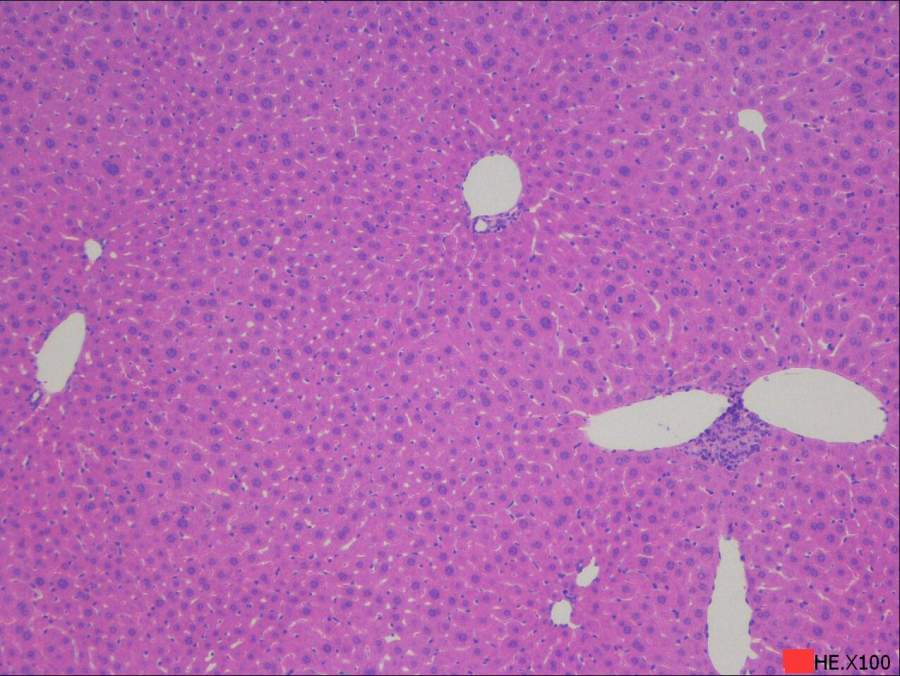

求助读片:小鼠肝脏HE切片(脂肪变性、炎症等)10周龄左右

由于肝脏病变相关知识储备不够,特请教各位虫友帮着读下片,主要想了解肝脏脂肪沉积、变性,是否有炎症等,如果有其它病变也请指点一下。在此不盛感激 !!!下面附图。 2.100.jpg 3.100.jpg 3.200.jpg 4.100.jpg 4.200.jpg 5.200.jpg@starseacow |